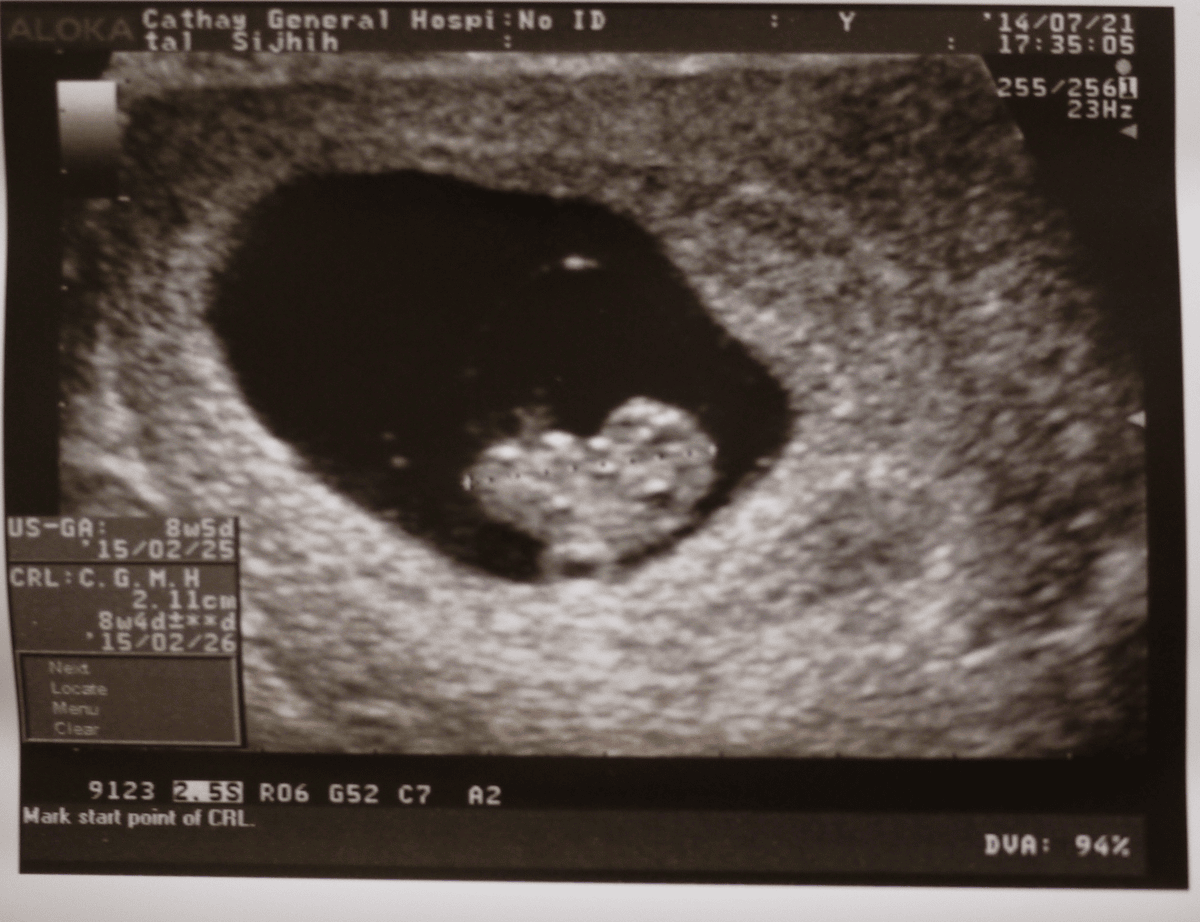

103/7/21(一)第二次產檢

這時的BABY已經有2.11CM了

在肚子上好像小豆子喔

這天照超音波,醫生也幫我看了BABY的頸部透明帶

還好只有1MM,醫生說這樣是正常的~接著就做第一孕期母血唐氏症篩檢

2.第二三次產檢我們都有聽心跳聲,聽到BABY的心跳聲真的好讓人感動喔

3.建議11~12週就可以做第一期唐氏症篩檢

4.單靠頸部透明帶的檢查,其實就可以篩檢出80%左右染色體異常的胎兒